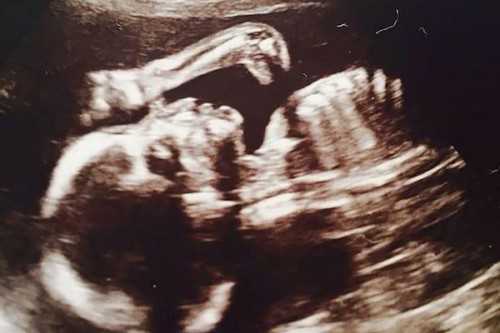

Сделавшая УЗИ беременная жительница Ливерпуля, 29-летняя Линн Салливан, обомлела, получив сюрприз из Юрского периода. Кроме малыша, она увидела на снимке шею и голову маленького динозавра.

Врачи в больнице, которые делали УЗИ, не обратили на длинную шею ящера никакого внимания. Первым заметил странное явление приятель Линн, Джеймс Флетчер. Он указал будущей матери на пятно, которое больше всего походило на крохотного бронтозавра – ископаемого ящера из Юрского периода.

Изумленная Линн Салливан поделилась загадочным снимком в Интернете. Она сообщила, что за пару недель до обследования ходила в кино на фильм “Парк Юрского периода”, премьера которого состоялась в начале июня.

На момент ультразвукового исследования ребенку было около 20 недель. Известно, что это девочка, которую родители хотят назвать Рути-Лу.